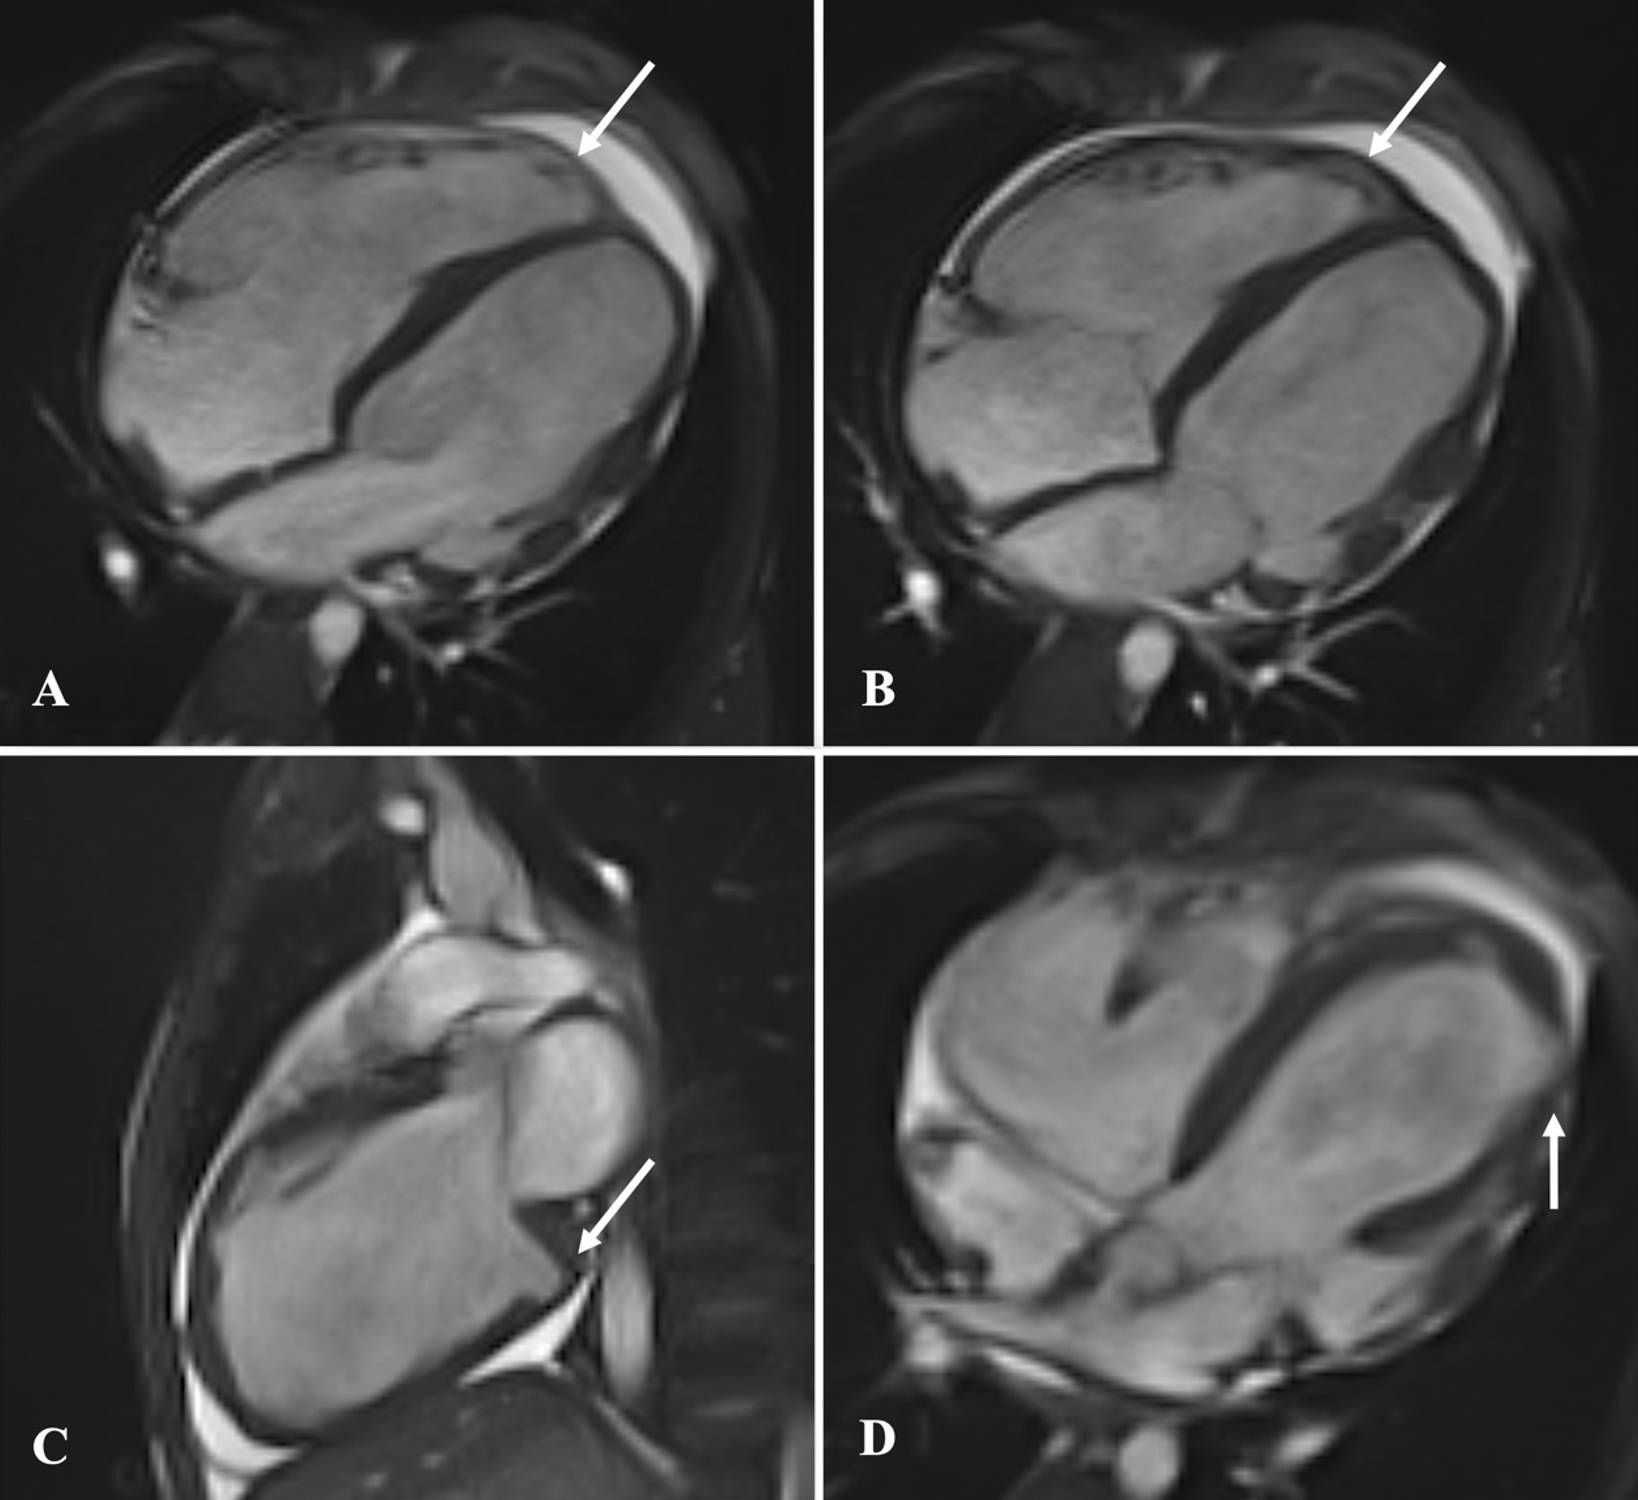

A 13-year-old male patient was admitted with complaints of chest pain and shortness of breath with exertion for 2 months. He was referred to our institution with a prediagnosis of ARVC and heart failure. Physical examination findings were as follows: Mild tachycardia (120-130 bpm), tachypnea (38/min), a 2-3/6 pansystolic murmur best heard at the left lower sternal border, jugular venous distension, a liver palpable 3 cm below the costal margin and mild ascites. Electrocardiogram showed; sinus tachycardia (110 bpm), a widened QRS (120 msec) and the corrected QT interval (QTc) of 480 msec (because of widened QRS) (Fig. 1). Echocardiography revealed significantly reduced biventricular function (left ventricle M-mode ejection fraction: 15%), enlarged right heart chambers with a RV diameter of 53.8 mm (z score: + 4.08) in apical 4 chamber view and severe tricuspid regurgitation (Fig. 2). Cardiac MRI showed marked dilation of the right ventricle (RV) with an indexed volume of 149 mL/m2 and hypokinesia in the free and inferior walls, as well as segmental wall thinning and focal late gadolinium enhancement (Fig. 3). The ejection fraction was 10% and 15% for the right and left ventricles, respectively. Heart failure treatment was administered immediately and a 24-hour-rhythm Holter was planned. On the second day of hospitalization, the patient had a sudden cardiac arrest and during cardiopulmonary resuscitation, it was recognized that the patient had VT exhibiting LBBB morphology with an intermittent transition to ventricular fibrillation (VF). Multiple antiarrhythmics including lidocaine, amiodarone, and magnesium were administered and the arrhythmia was converted to sinus rhythm after 5 cardioversions and 2 defibrillations. The patient was transferred to the pediatric intensive care unit (PICU). During follow-up in the PICU, the patient had episodes of LBBB morphology VT with intermittent transition to VF despite amiodarone and lidocaine infusion and was re-arrested. During cardiopulmonary resuscitation (CPR), venoarterial extracorporeal membrane oxygenation (ECMO) was initiated in 35 minutes. As drug-resistant VT storm continued during ECMO support, a single staged endocardial and epicardial approach for ablation was planned along with the assistance of cardiothoracic surgery. Even though the epicardial scar was much larger than the endocardial scar, a clinical VT isthmus was present at the endocardial site where ablation terminated the VT quickly (Fig. 4). An implantable cardiac defibrillator was implanted for secondary prevention, amiodarone was administered, and the patient was decannulated on the 4th day. The patient was discharged without any sequelae meanwhile autosomal dominant mutation that is linked to ARVC was detected in DSC2 gene at 18q12.1. Three months later the patient was rehospitalized for decompensated heart failure (NYHA class III-IV). Following this, his clinical status deteriorated due to multidrug refractory and inotrope-dependent heart failure. His kidney functions worsened, he became symptomatic even at rest, and developed massive hepatomegaly and ascites which required multiple paracentesis but never experienced sustained and hemodynamically significant arrhythmia. He could not be discharged and was on inotropes for 12 months till he underwent a successful heart transplantation. Pathological analysis of the explanted heart revealed: diffuse degenerative changes characterized by nuclear hyperchromasia, centralization and pleomorphism, areas of mucinous degeneration and oedema under the endocardium, mucinous degeneration in the valves, fibrosis between muscle fibers, congestion and fibrin accumulation sites in the pericardium and also a quite thin right ventricle wall. The patient has been followed up for 9 months and shown no symptoms post-transplantation.